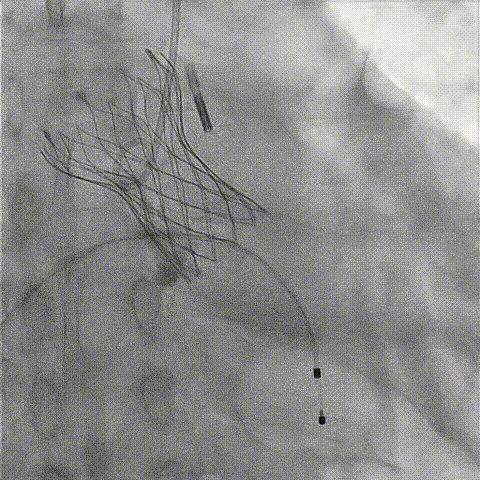

根部造影

球囊预扩

释放工作位造影

后扩后造影